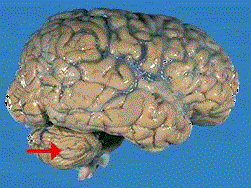

如图箭头所示为大脑哪个部位 ( ) A、脑干B、额叶C、枕叶D、小脑E、顶叶

问题 如图箭头所示为大脑哪个部位 ( )

选项 A、脑干 B、额叶 C、枕叶 D、小脑 E、顶叶

答案 D